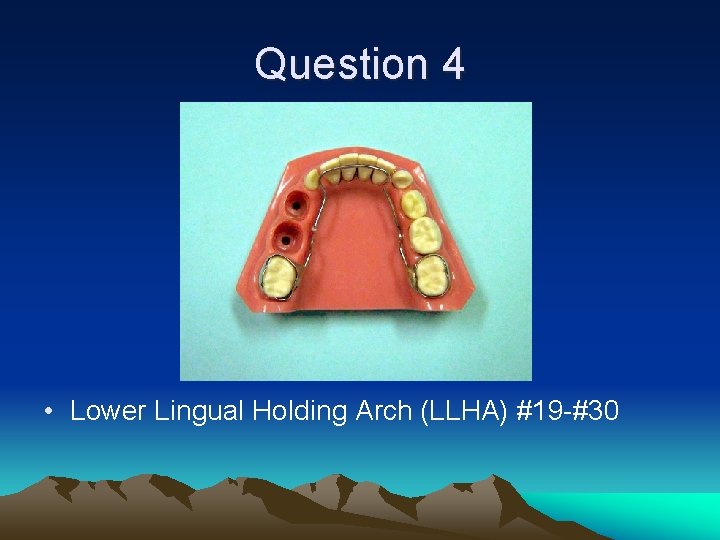

Question 4 • Which teeth were extracted/ • What is the appropriate space maintainer?

Question 4 • Lower Lingual Holding Arch (LLHA) #19 -#30